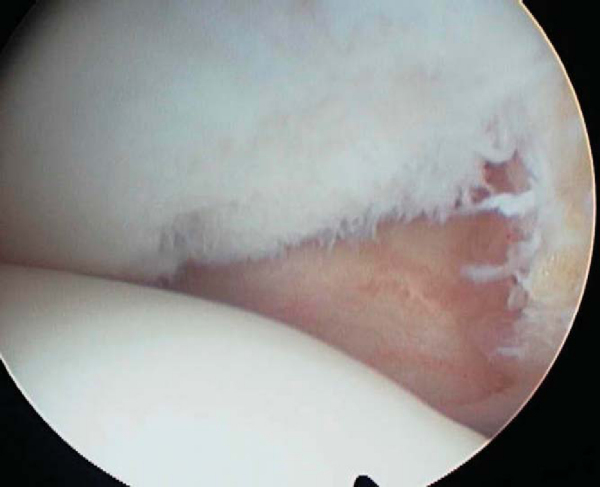

), and the defect and its borders are carefully and systematically palpated with a blunt probe. This will expose loose flaps and any areas of delamination. It is also important to identify areas where the cartilage is softened (

Fig. 51-3

); but if the cartilage has an intact surface, it should not be débrided. Once loose flaps of cartilage are identified, a 4.5-mm aggressive shaver is placed, and the loose flaps and debris are mechanically removed until stable borders are obtained (Figs. 51-4 and 51-5 [4] [5]). A whisker-type shaver may also be used for less aggressive débridement. Care must be taken not to peel off the articular cartilage but only to remove the unstable borders. The posteromedial and posterolateral gutters are also visualized to evaluate for intraarticular loose bodies. The blunt arthroscopy obturator is placed through the notch into the posterolateral and posteromedial recess of the knee under direct visualization. Once it is in position, the camera is then placed into the obturator sleeve, and the posterolateral and posteromedial notch recesses are visualized.

Figure 51-3 |